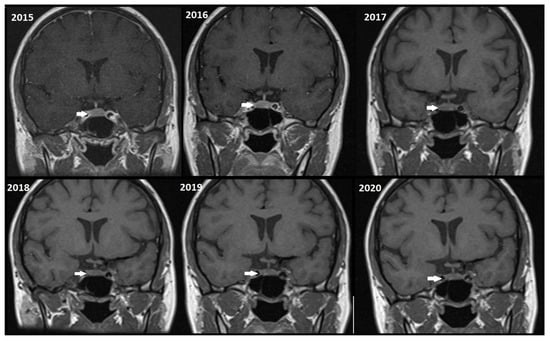

Although, the main cohort contained patients referred between 2020 and 2024, Figure 2, Figure 3 and Figure 4 shows a representative case with historical scans (2015–2020), retrieved from PACS, to demonstrate temporal stability. No evidence of recurrence of tumors in any of the nine who underwent resection of macroadenomas during this period was seen.

Figure 2.

Representative coronal images (2015–2020) of a stable microadenoma (arrows) of a 33 Y/O woman. The left upper image from 2015 is a delayed image, and the other six images are dynamic MRI follow-ups for this patient. In 2017, the patient had two follow-ups in the first and second half of the year. In the 5 years of follow-up, no size change can be seen.

Moreover, repeated exposure to gadolinium is associated with the deposition in basal ganglia and the dentate nuclei of the cerebellum. This deposition results in an increased signal intensity seen in T1-weighted imaging that has raised concerns concerning potential long-term neurological effects. These safety concerns are thus especially important in the case of patients with microadenomas who may require repeated MRI surveillance [38,39]. Given the fact that patients with microadenoma may be exposed more frequently to MRI with contrast, our study investigated conventional MRI and dynamic imaging for diagnosis and follow-up in patients with pituitary microadenomas undergoing MRI at our institution. We also evaluated the change in size of microadenomas in follow-up MRI studies and the necessity of injecting contrast media in monitoring this set of patients (Figure 2, Figure 3 and Figure 4).